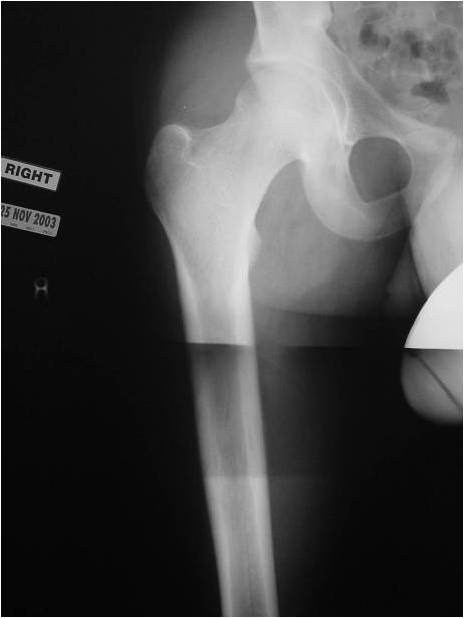

- Most commonly arises from diaphysis but can also arise from metadiaphysis and metaphysis;

- Very rare epiphyseal involvement

- Long Bones – Most common

- Femur: Single most common site

- Permeative or moth eaten bone destruction

- Ill defined and malignant appearing

- Bony changes are often subtle

- Pathologic fracture in 10-15%